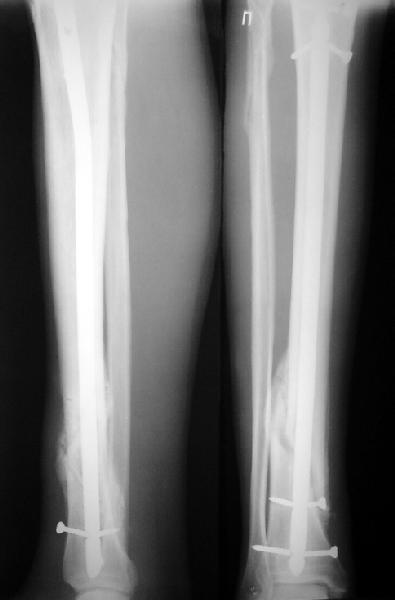

На мой взгляд, на снимках, приведённых Вами - неправильно сростающийся перелом дистальной трети большеберцовой кости, состояние после остеосинтеза интрамедуллярным гвоздём.

Как Вы пишите снимок под номером 1 - менсяц после операции, под номером 2- два месяца после операции.

Вы не послали послеоперационный снимок, поэтому трудно судить о состоянии редукции после операции.

Позвольте по поводу техники операции высказать своё мнение...

Установка с медиальной стороны гвоздя в области дистального фрагмента дополнительного шурупа помогло бы Вам репонировать и удержать перелом в анатомическом положении, предотвратило варусную деформацию и смещение по ширине.

Кстати, если можно пошлите послеоперационный снимок.

На мой взгляд внутрикостная фиксация переломов дистальной и проксимальной трети большеберцовой кости, за исключением поперечных, не очень хорошее решение вопроса, аппарат Илизарова или Тэйлора, позволяющие призвести закрытую анатомическую редукцию и отличное удержание отломков в период сращения.

Пример, приведённый Вами в нашей дискуссии по времени нагрузки после остеосинтеза не совсем удачный... Ваш больной имеет счастье, что первым согнулся проксимальный замыкающий винт, а не дистальный и гвоздь не пенетрировал голеностопный сустав.

JOM> Кстати, если можно пошлите послеоперационный снимок.

Ok. А также и следующий, в 3 месяца.

Это наглядная демонстрация возможности ранней полной нагрузки при нестабильном по оси повреждении, причем не в самых благоприятных механических условиях - при плохом сопоставлении, со слабым фиксатором.

Сверху - один статический винт, а снизу - три. Что раньше сломается? Конечно, он потом и нижние сломал, и Вы правы, если бы верхний динамичесий винт уже уперся бы в нижний край отверстия, будь гвоздь подлинее, перфорировал бы сустав как пить дать.

Как я уже говорил, мы сделали выводы из этого и других подобных случаев. Очевидно, решений проблемы два - либо уменьшить нагрузку, либо увеличить прочность фиксатора. Первое решение работает не со всеми больными, так что пошли по второму пути - мы больше не используем гвозди с запирающими винтами диаметром 4 мм.